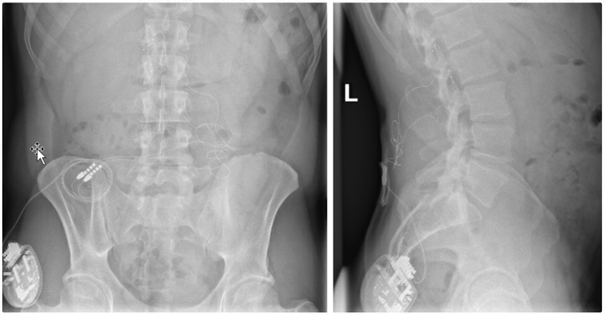

Bei der Rückenmarkstimulation wird in der Wirbelsäule eine Elektrode platziert. Über diese werden elektrische Impulse an das Rückenmark abgegeben. Die Elektrode ist mit einem Impulsgeber (vergleichbar mit einem Herzschrittmacher) verbunden. Das operative Verfahren gliedert sich in zwei Abschnitte: Im ersten Eingriff erfolgt, unter örtlicher Betäubung und Röntgenkontrolle, die Platzierung der Elektrode im Rückenmarkskanal. Im Anschluss erfolgt eine Testphase. Ziel ist es, die Abdeckung des Schmerzareals durch die Stimulation und die daraus resultierende Schmerzreduktion zu testen. Bei zufriedenstellendem Ergebnis wird in einem zweiten Eingriff der Impulsgeber unter die Haut implantiert.

Röntgenbild zur Rückenmarkstimulation

Das Pumpensystem besteht aus einem kleinen Schlauch, welcher in den Nervenwasserraum eingebracht wird und mit der Pumpe verbunden ist. Die Pumpe wird meist am Bauch unter der Haut implantiert und ermöglicht, dass die Dosierung der Medikamente exakt an die Bedürfnisse angepasst werden kann. Es ist eine regelmäßige Wiederbefüllung der Pumpe mit den Medikamenten notwendig, was ähnlich wie bei einer Blutabnahme von außen erfolgt.

Am Bauch implantierte Medikamentenpumpe (Pfeil)